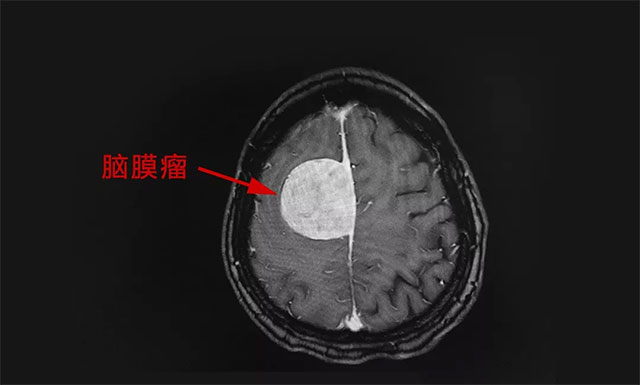

為完善其檢查,郭女士做了頭部 MRI 檢查,結(jié)合其病史、病癥及影像學(xué)結(jié)果,患者郭女士被診斷為:右側(cè)額葉大腦凸面腦膜瘤,腫瘤大小約為 4.5cm x 4.4cm x 4.0cm ,如雞蛋般大小。

▲ 標(biāo)記處為腦膜瘤

潘仁龍主任表示,一般腦膜瘤在 2厘米以內(nèi)是屬于比較小的腦膜瘤,而這樣大的腦膜瘤 (4.5cmx4.4cmx4.0cm) 還是比較少見(jiàn)的,由于腫瘤已經(jīng)壓迫到周圍的腦神經(jīng)和血管,同時(shí)又是在大腦功能區(qū),已嚴(yán)重影響到患者走路及肢體的活動(dòng),加之其頭痛厲害,手術(shù)指征明顯,應(yīng)盡早手術(shù)。